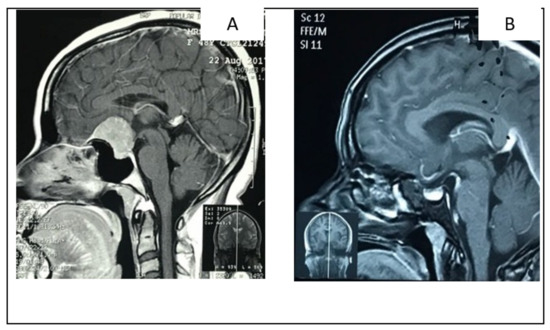

2.1.2. Illustrative Case: 1

2.2.2. Illustrative Case 2